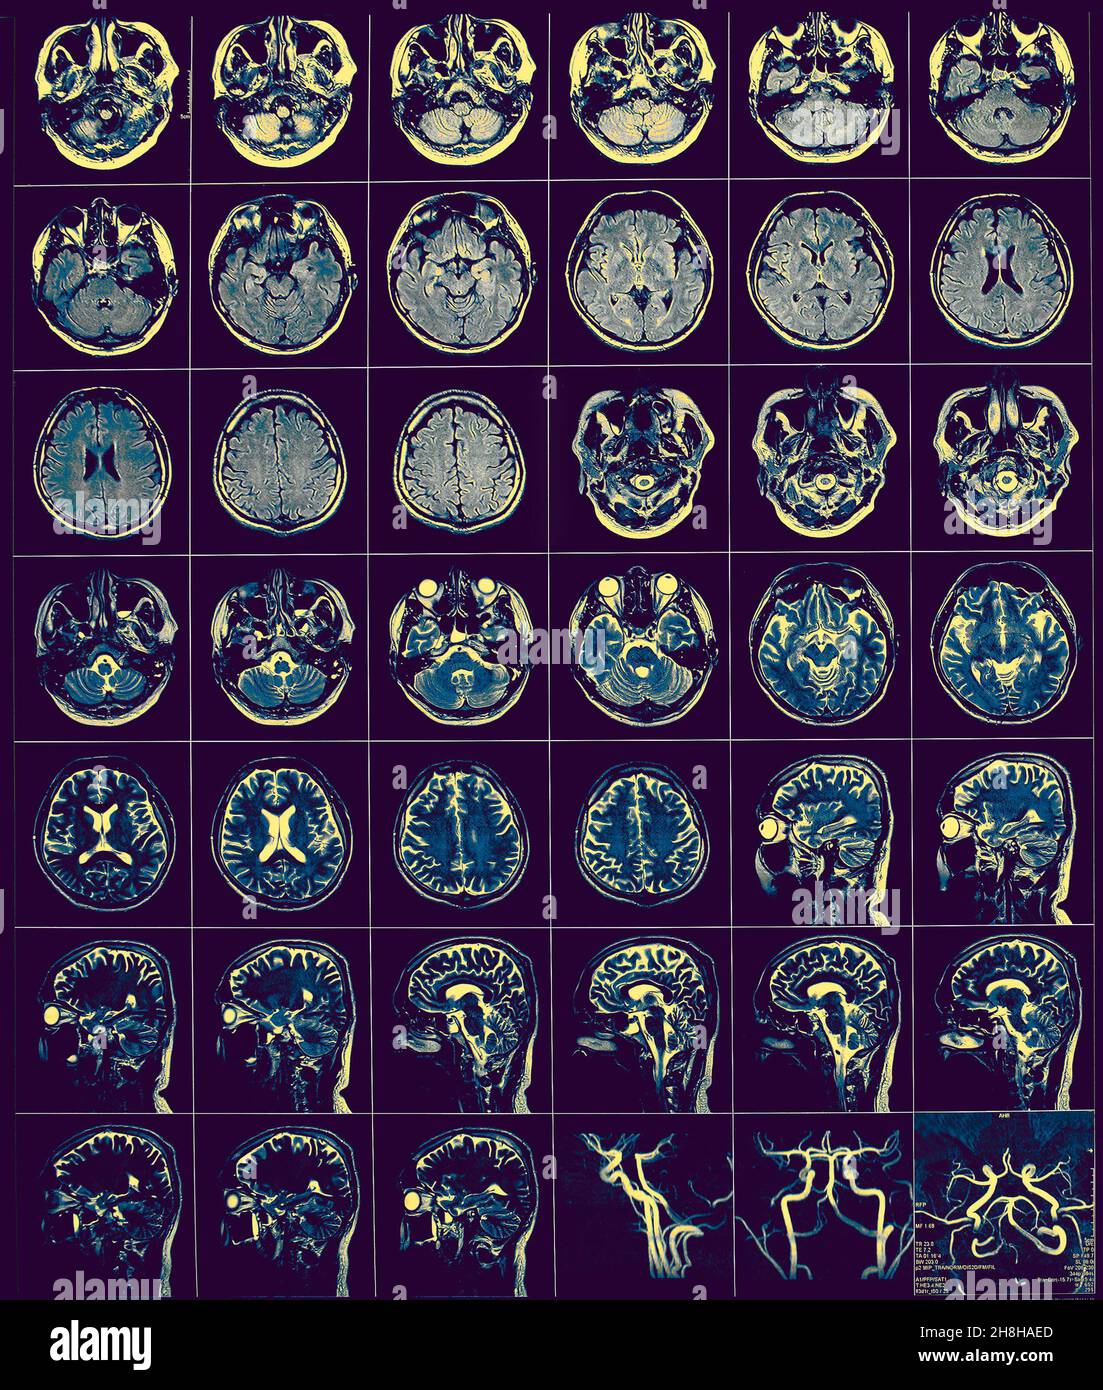

Film CT comme base de diagnostic médical. Banque D'Imageshttps://www.alamyimages.fr/image-license-details/?v=1https://www.alamyimages.fr/film-ct-comme-base-de-diagnostic-medical-image452768245.html

Film CT comme base de diagnostic médical. Banque D'Imageshttps://www.alamyimages.fr/image-license-details/?v=1https://www.alamyimages.fr/film-ct-comme-base-de-diagnostic-medical-image452768245.htmlRF2H8HAED–Film CT comme base de diagnostic médical.